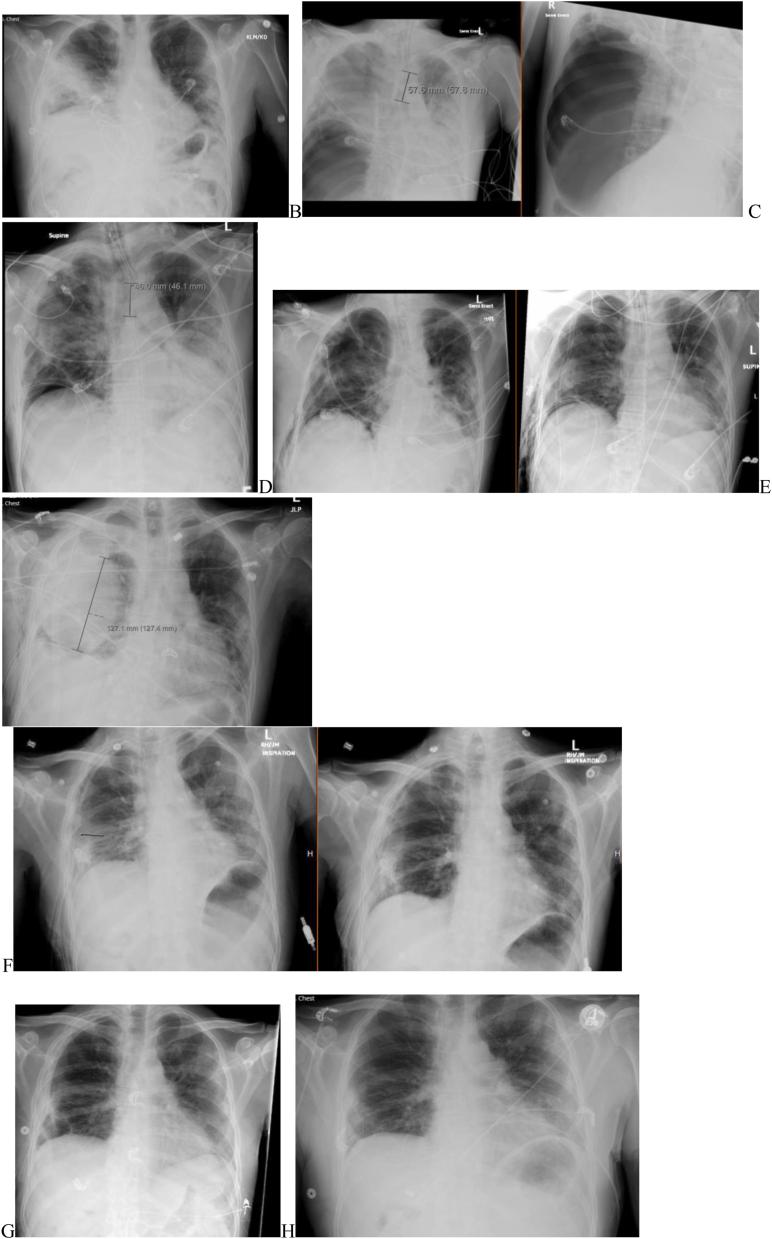

An air leak is a pathologic communication between an area of the endobronchial tree and the pleural space, causing continued air flow. The communication can originate from a distal portion of the airway, causing an alveolar-pleural fistula, or from a more proximal airway, causing a bronchopleural fistula. When the air leak persists beyond 5-7 days, it is classified as persistent air leak (PAL). PAL has serious implications on patient management and outcomes, such as prolonged chest tube maintenance, high rate of infections, ventilation-perfusion mismatch, and prolonged hospital stay with higher morbidity and mortality. There are currently no guidelines for the management of PAL in COVID-19 patients. We presented a case of PAL in a patient with COVID-19-associated pneumothorax successfully treated with a one-way endobronchial valve. We also reviewed current published cases of PAL secondary to COVID-19-associated pneumothorax and the various methods they were treated. The first line treatment was insertion of one or more chest tubes, but the persistence of an air leak then led to other treatment modalities. Initial early surgical evaluation followed by pleurodesis is recommended for the management of PAL. The most common surgical approaches include VATS or open thoracotomy with mechanical or chemical pleurodesis or pleurectomy. However, surgery is not always a feasible option for critically ill patients. In such cases, there are multiple less invasive options for the management of PAL, including implantable devices, such as Watanabe spigots and stents, and chemical agents, such as thermal treatments, hemostatic substances, and tissue adhesives.

空气泄漏是支气管树区域与胸膜腔之间的病理性交通,导致持续的气流。这种交通可起源于气道的远端部分,导致肺泡-胸膜瘘,或起源于更近端的气道,导致支气管胸膜瘘。当空气泄漏持续超过5至7天时,被归类为持续性空气泄漏(PAL)。PAL对患者的管理和预后有严重影响,如胸腔闭式引流管留置时间延长、感染率高、通气-灌注不匹配以及住院时间延长,发病率和死亡率更高。目前尚无针对COVID-19患者PAL管理的指南。我们报告了一例COVID-19相关性气胸患者发生PAL并成功接受单向支气管内瓣膜治疗的病例。我们还回顾了目前已发表的继发于COVID-19相关性气胸的PAL病例及其接受的各种治疗方法。一线治疗是插入一根或多根胸腔闭式引流管,但空气泄漏持续存在会导致采用其他治疗方式。对于PAL的管理,建议早期进行手术评估,随后进行胸膜固定术。最常见的手术方法包括电视辅助胸腔镜手术(VATS)或开胸手术,并进行机械或化学胸膜固定术或胸膜切除术。然而,对于重症患者,手术并不总是可行的选择。在这种情况下,有多种侵入性较小的PAL管理选择,包括可植入装置,如渡边套管和支架,以及化学制剂,如热治疗、止血物质和组织粘合剂。